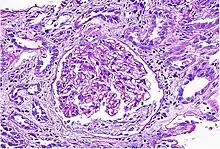

Acute interstitial nephritis on light microscopy | |

While non-invasive patient evaluation (physical examination, blood and urine testing, imaging studies) can be suggestive, the only way to definitively diagnosis interstitial nephritis is with a tissue diagnosis obtained by kidney biopsy. Pathologic examination will reveal the presence of interstitial edema and inflammatory infiltration with various white blood cells, including neutrophils, eosinophils, and lymphocytes. Generally, blood vessels and glomeruli are not affected. Electron microscopy shows mitochondrial damage in the tubular epithelial cells, vacuoles in the cytoplasm, and enlarged endoplasmic reticulum.[23]